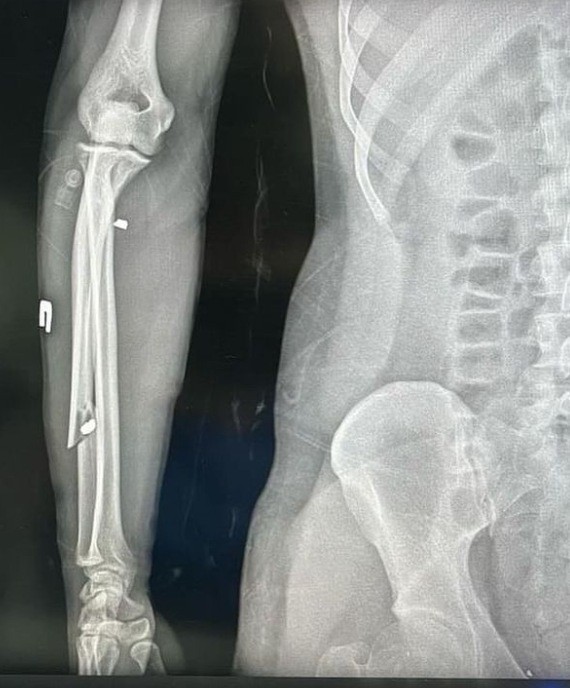

Юлія Чуйко, подруга Юри, що 15 років тому танцювала з ним в танцювальному колективі “Inside”, написала в Інстаграм, що він отримав важкі поранення: «Безліч уламків, зламана рука, струс мозку, сильно поранені ноги. Поки що він не встає з ліжка. Треба в прямому сенсі ставити на ноги, нашого захисника! Знаючи Юру, як тільки він відновиться, то знову повернеться на фронт. Тому ми маємо допомогти фінансово».